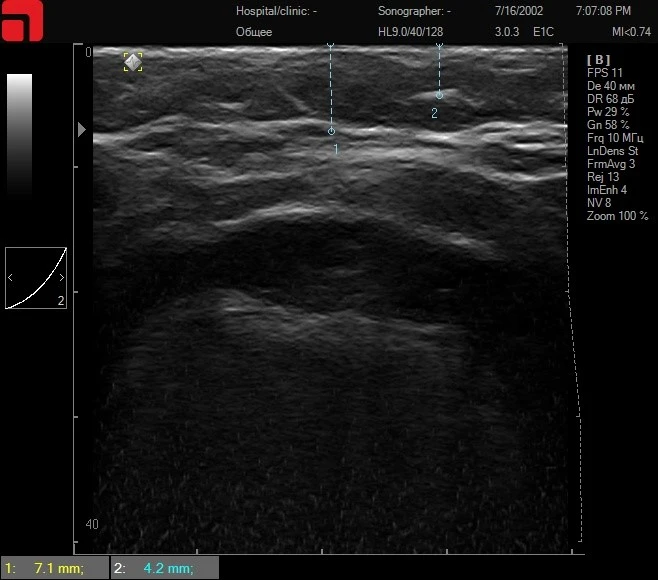

Из анамнеза: в 2018 году проводилась процедура нитевого лифтинга. Моментальный эффект был хорошим, но сохранялся непродолжительное время – 2 недели. Противопоказаний не выявлено, практически здорова. Усталый тип старения, птоз тканей незначительный, но доставляет большой дискомфорт пациентке. На этапе ультразвуковой диагностики выявлено резкое снижение количества соединительной ткани на уровне подкожно-жировой клетчатки и SMAS.

Принято решение проводить курс лечения в два этапа. На первом этапе процедура коллагенстимуляции препаратом полимолочной кислоты, после периода биодеградации – процедура SMAS-лифтинга.

Рис. 6. Сканограмма до процедуры коллагенстимуляции, отмечается резко сниженное количество соединительной ткани в подкожно-жировой клетчатке и на SMAS.

Рис. 7. Сканограммы через 6 месяцев после процедуры коллагенстимуляции. Отмечается уплотнение кожи, соединительной ткани в подкожно-жировой клетчатке.